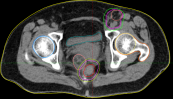

病例展示二:前列腺癌

XXX,男,64岁,主诉:间断性会阴部疼痛10月,确诊为前列腺癌7月。盆腔核磁:前列腺偏左侧异常强化占位,多考虑前列腺Ca,并左侧精囊腺受侵可能,盆腔左侧略大淋巴结。前列腺癌标志物提示:TPSA 88.67 ng/ml,FPSA 3.84 ng/ml。病检:(前列腺穿刺组织左侧)前列腺腺泡腺癌,Gleason评分4+3=7分;(前列腺穿刺组织右侧)Gleason评分3+3=6分。诊断:1、前列腺恶性肿瘤 双侧 腺泡腺癌Gleason评分4+3 =7分 cT3bN0M0 III期 KPS评分:80分。治疗方案:醋酸戈舍瑞林缓释植入剂 10.8mg 皮下注射、比卡鲁胺胶囊 50mg 口服 1次/天”全身治疗,并行前列腺癌碳离子治疗,剂量:57.6 Gy(RBE)/16 Fx。